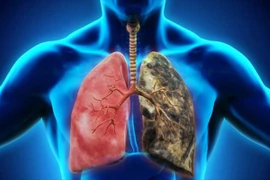

Phổi đảm nhận nhiệm vụ hô hấp và cung cấp khí oxy cho hồng cầu, đảm bảo duy trì sự sống của con người. Tuy nhiên, nhiều thói quen hàng ngày mà chúng ta thường không để ý đến có thể gây hại cho sức khỏe của phổi.

Mặc dù hầu hết mọi người đều nhận thức được sự nguy hiểm của việc hút thuốc đối với cơ thể nhưng vẫn có những người hút thuốc và phớt lờ những lời khuyên.

Trong nỗ lực ngừa ung thư phổi, từ bỏ thói quen hút thuốc lá là một trong những yếu tố không thể thiếu. Ngoài ra, bạn có thể tăng khả năng ngăn ngừa ung thư phổi bằng việc thường xuyên ăn những thực phẩm dưới đây.